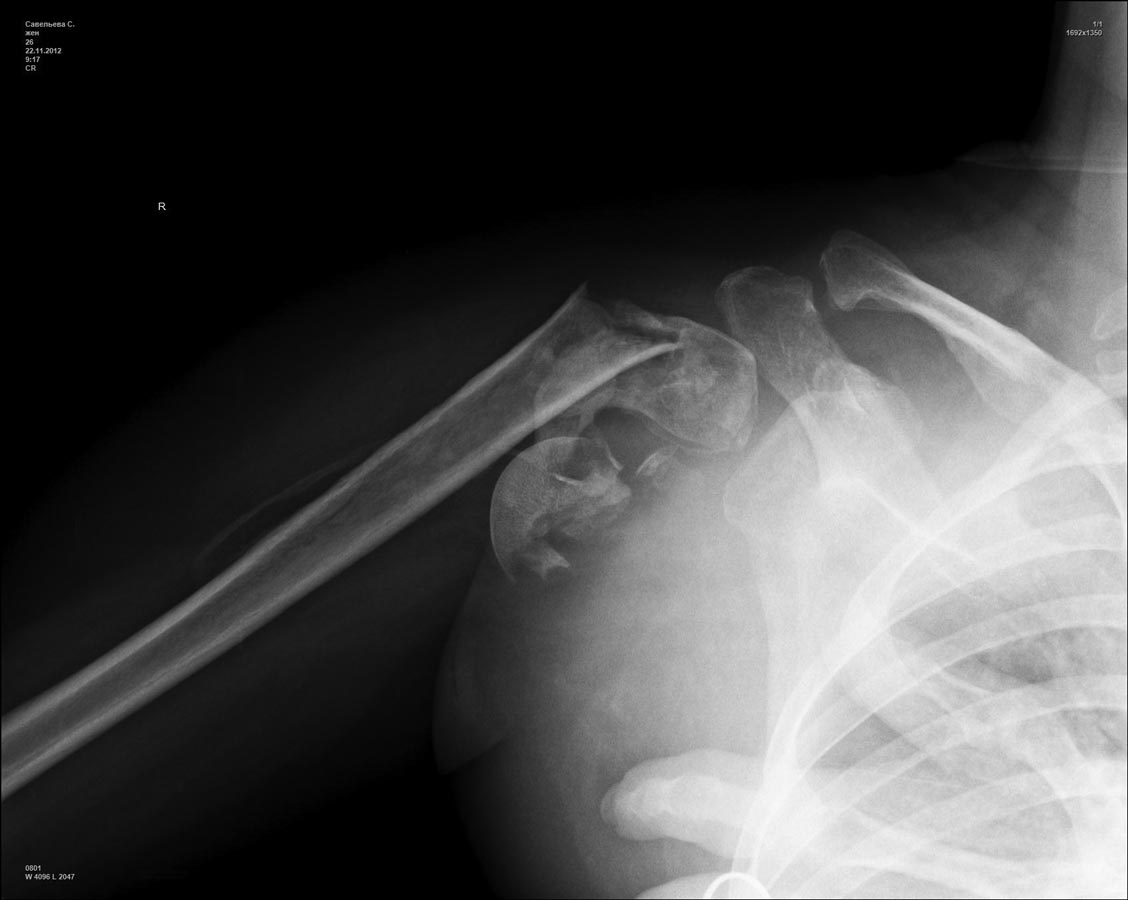

Девушка 26 лет. 4 месяца после травмы. Неправильно срастающийся многооскольчатый перелом проксимального эпиметафиза правого плеча.

Посттравматическая плексопатия.

Доп.информация: открытый (IIA) перелом диафиза и шейки правого бедра через 2 мес. после травмы синтезированы рекон. стержнем. После операции абсцесс правого бедра (все воспалительные явления регрессировали).

В отделении возникли разногласия по тактике лечения. Доступны практически любые имплантаты, в том числе и протезы. Будем признательны за помощь в выборе тактики. Заранее спасибо.